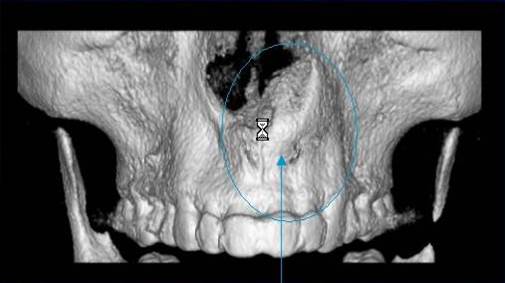

Je speciální zubní digitální tříprostorový tomograf (3D), který umožňuje na základě jediného snímkování vytvořit všechny typy RTG zobrazení, které jsou pro lékaře potřebné. Díky používané technologii tzv. „kuželového paprsku“ a speciálním senzorům je výrazně zmenšená dávka záření - o více jak 80% proti klasickému CT vyšetření. To je významné zejména u dětí. Pomocí tohoto přístroje je možné zjisti skutečnou situaci v čelistních kostech pacienta tedy množství kosti - můžeme změřit skutečnou šířku i výšku kosti, i kvalitu kosti (hustotu) v místě uvažované implantace. 3D (tříprostorové) zobrazení umožňuje zvýšit prostorovou představu operatéra ještě před vlastní operací a zároveň pacientovi lépe objasnit a ukázat oblast plánovaného zavedení implantátu.

Pacient „neumí číst“ RTG snímky, ale díky 3D zobrazení vidí „svoji skutečnou čelist“ - např. jak je nízká či úzká, vidí průběh nervu nebo velikost čelistní dutiny, což mu umožní i pochopení nutnosti v některých případech provést pomocné zákroky ještě před vlastním zavedením implantátu (viz. kostní štěp, sinus lift, kostní granulát...).

Vyšetření pomocí tohoto přístroje používáme i ve stomatochirurgii (zlomeniny čelistí, zuby moudrosti, cysty, onemocnění čelistního kloubu), ortodoncii (retinované zuby, nadpočetné zuby), parodontologii atd.